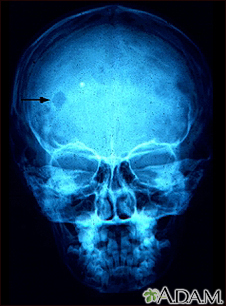

Eosinophilic granuloma - x-ray of the skullBackEosinophilic granuloma - x-ray of the skullThis x-ray of the skull shows an eosinophilic granuloma (a lesion made-up of a type of white blood cell). This condition can range from a single eosinophilic granuloma to massive infiltration of skin, bone, and body organs. E-mail FormEmail ResultsName:Email address:Recipients Name:Recipients address:Message: